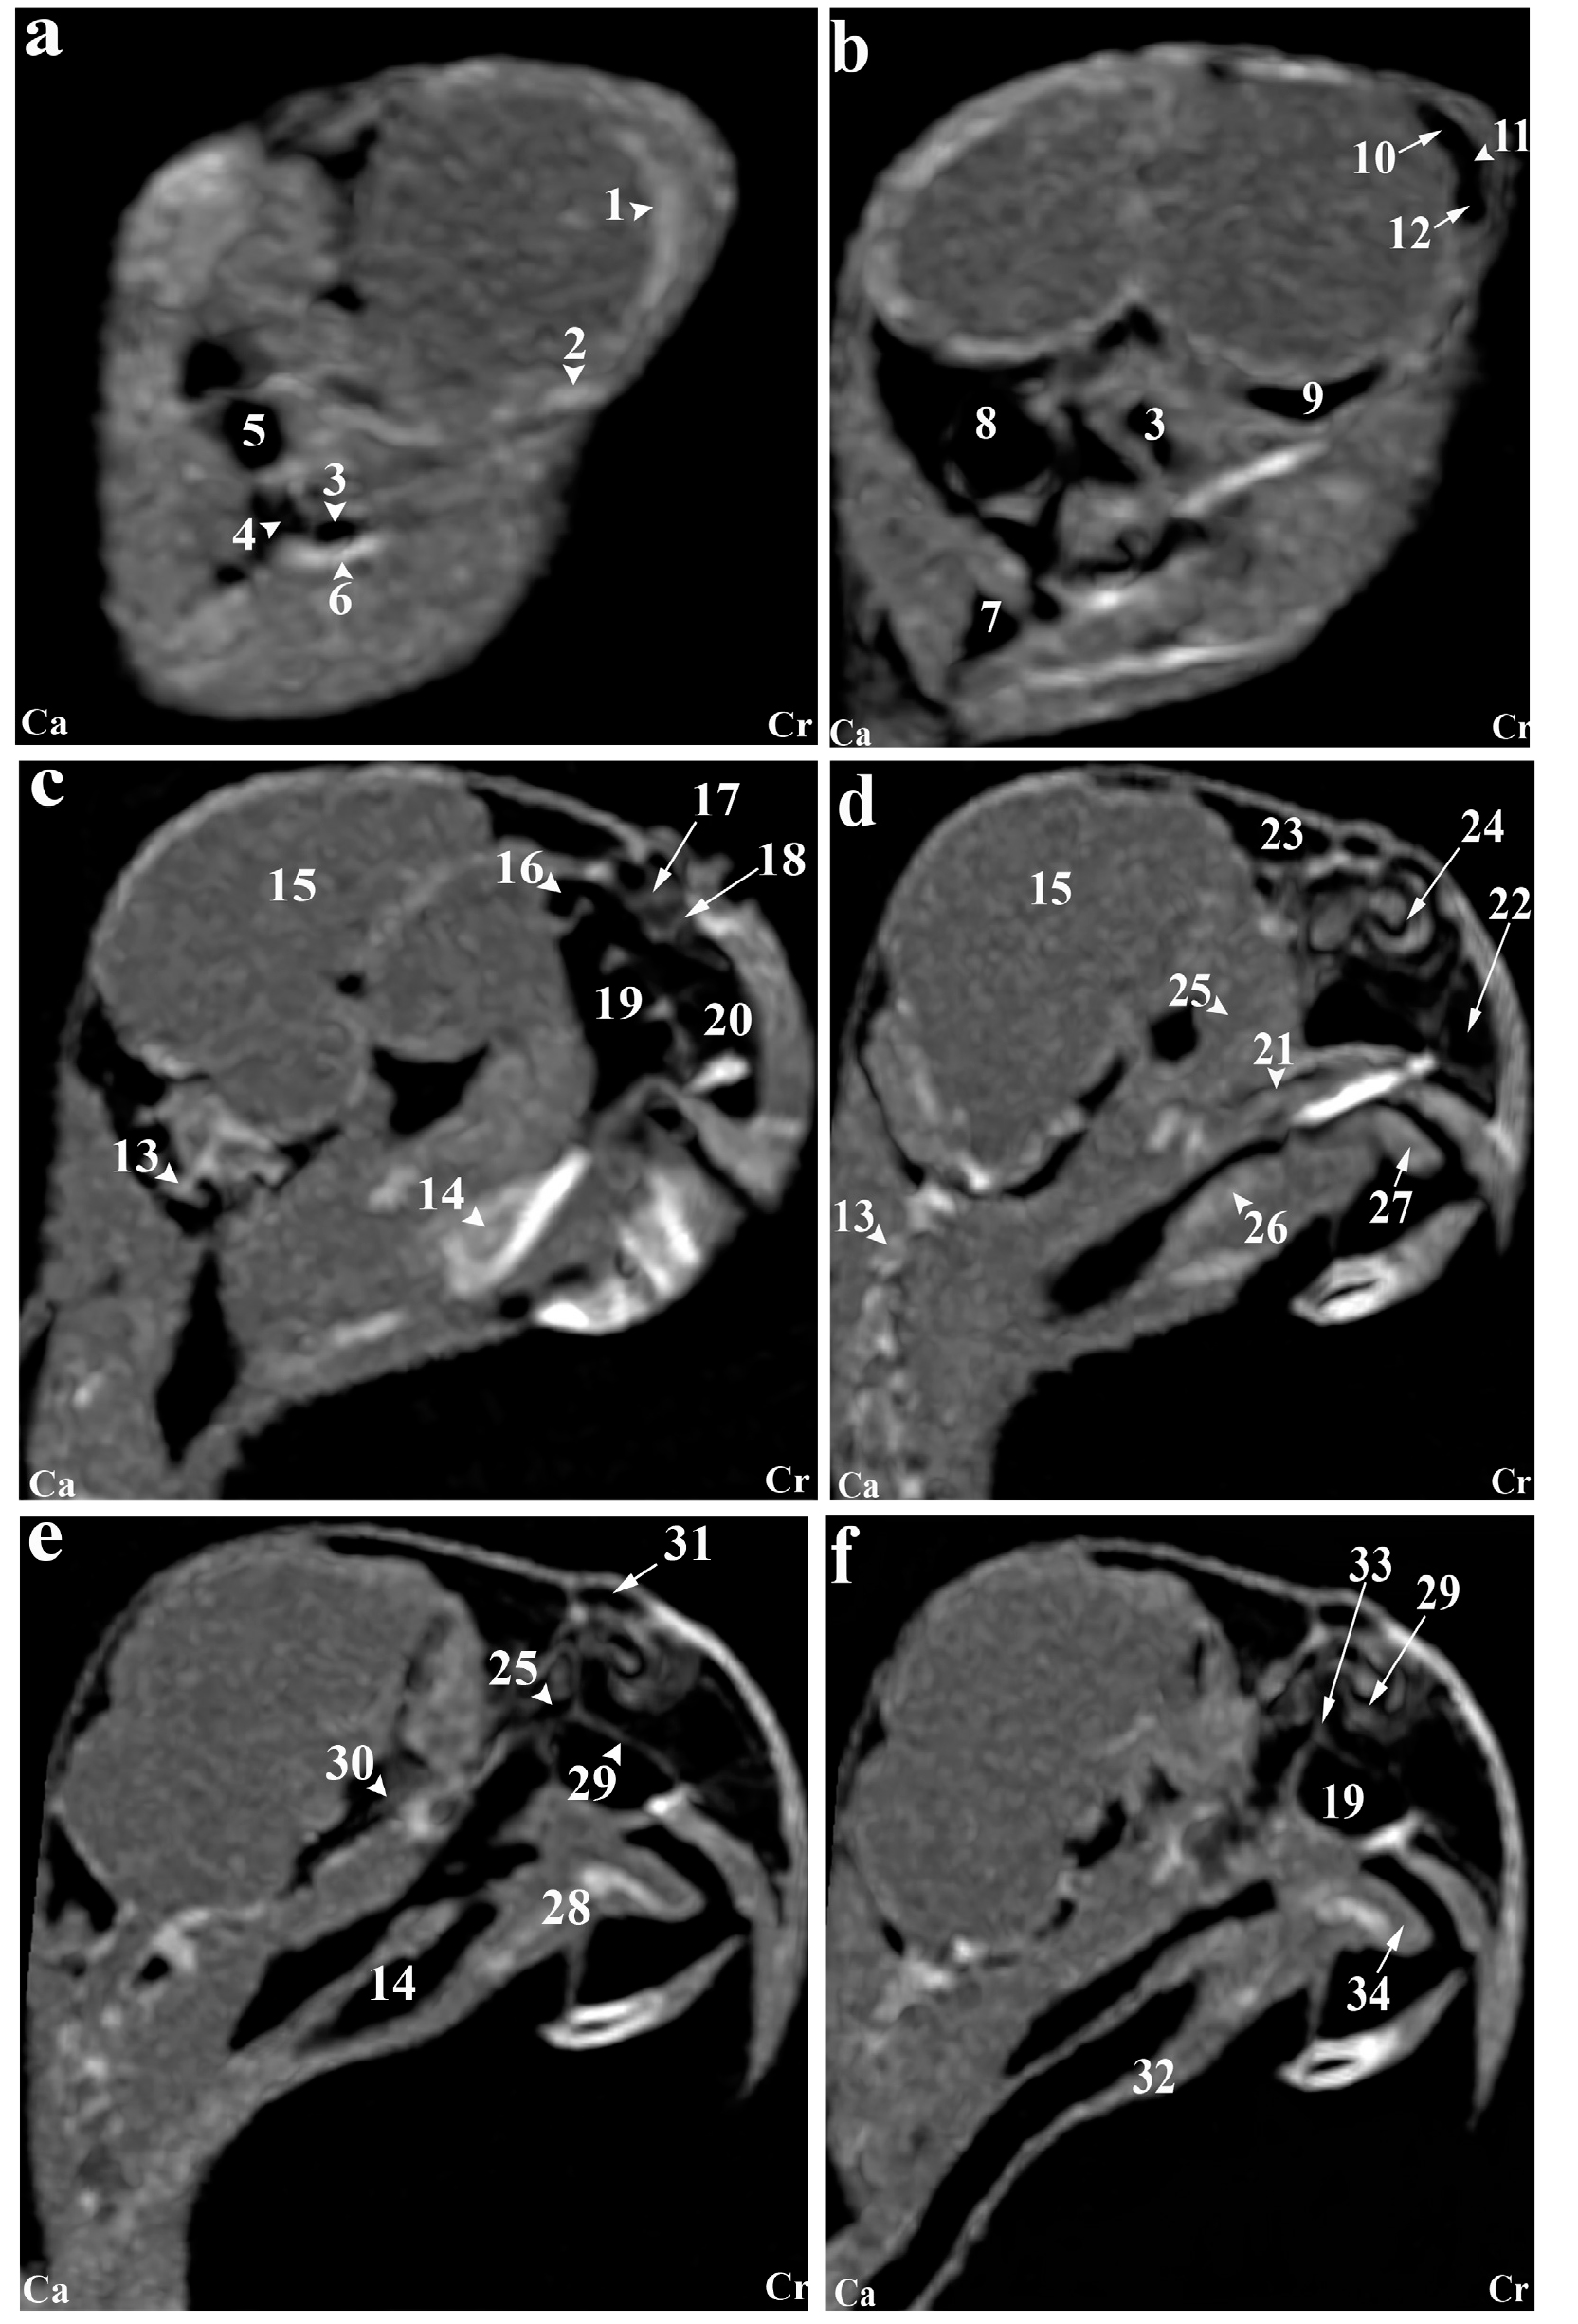

Reconstructed CT images revealed that most structures of the head of the Rose-ringed parakeet (Psittacula krameri) were identifiable. In the 3D images, the parrot's head appeared rounded and compact. The jugal arch and the palatine bone were fused in the remaining parts of the skull, except for the cranial facial bones. Even small bones of the head, such as ear bones and entoglossal bones inside the mouth, could also be evaluated in these CT images. Using the lung window filter, it was possible to observe the bony trabecular in the head. This setting also enabled evaluation of the parietal and temporal bones, nasal conchae, epithelial membranes, the external ear canal, and bony labyrinth. Further, with covering tissues, different parts of the infraorbital sinus could be observed using this filter. Furthermore, different soft tissue windows were adjusted to allow for the identification of brain hemispheres, the cerebellum, optic nerve, pupil muscles, and eye lenses (Figures 2-3). Based on the findings, the columella ossicle, its external cartilage, and the cochlea were not detectable on CT. The eyeballs of all parrots were complete and bony and located on the skull's lateral side (Figure 2i). The mandible appeared bony and lacked a distinct symphysis (Figures 2b and 3a), while the rostrum was keratinous, large, and ventrally curved. The operculum was observed on the dorsal base of the nostrils. Bones such as occipital, maxillary, premaxillary, mandible, palatine, pterygoid, and quadrate were pneumonized and had air bubbles. The nasal cavities were divided by a septum, which thickened slightly from the rostral to the caudal side. Its caudal third was cartilaginous, while the middle third and the rostral were bony. The ectethmoid, mesethmoid, maxillary, and preimaxillary bones were involved in the formation of the nasal cavity, and the nasal cavity comprised three parts: olfactory, respiratory, and vestibular. Each nasal cavity had a single duct with caudal, middle, and rostral cartilaginous conchae. The rostral concha C-shaped and located in the vestibular part of the nasal cavity decreased in thickness from the rostral to the caudal direction and contained a basal lamella along the lateral nasal cavity wall. The middle concha was in the form of long ducts that originated from a basal lamella and was located in the upper respiratory tract of the nasal cavity. This lamella also splits into a sinusoidal and a spiral lamella. The spiral lamella extended to the entrance of the nasopharyngeal canal. The caudal concha, smaller and hollow, was located at the nasal cavity's rear. The nasal and oral cavities were connected through the nasopharyngeal canal (Figures 3c and 4h), which connected the maxilla-palatal process and the palatine bone's choanal part from the rostro-lateral and caudal sides. The caudal part of this duct linked with the interorbital septum (Figures 3e and 4f). The oral cavity included the palatal, mandible, premaxillary, and maxillary bones, along with associated muscles and tongue. These bones, along with the pterygoid, contributed to pharynx formation (Figures 4c-d). The choana was located in the dorsal part of the pharynx and oral cavity and connected the oral cavity to the nasal cavity (Figures 2g). The tongue was strong and large, and could be identified in the CT images, located in the middle third and caudal of the inferior part of the oral cavity (Figures 2c-d). The oral cavity had a hyobranchial apparatus. The tongue's base was in close contact with the paraglossum and the cranial part of the basihyal. Bishyal processes and uhorial bones were detectable in the trachea's larynx and cranial part. The branchial horn (caudal part of the hyobranchial apparatus) was located in the inner part of mandible's ramus, or tracheal cranial part. Its caudal third was associated with mandible masseter muscles. The larynx consisted of a ring-shaped cricoid cartilage and two pyramid-shaped arytenoid cartilages. The results of the current study demonstrated that the procricoid cartilage was located within the middle part of the cricoid cartilage and formed the larynx 's dorsocaudal part (Figures 2b-j). The glottis was centrally placed in the larynx and surrounded by arytenoid cartilages. While laryngeal mounds (Mons laryngealis) were visible in CT cross-sectional. The place where the cricoid joins the tracheal cartilages also appeared ring-shaped in these images (Figures 2f and 4f).

Figure 3. (a-n) Transverse computed tomography reconstruction images in the lateral plane of the normal skull of the cockatiel (Nymphicus hollandicus). (1) Rostral diverticulum septum, (2) Premaxillary bone, (3) Rostral diverticulum, (4) Paraglossum, (5) Bony part of nasal septum, (6) Mandible bone (pneumonized), (7) Palate bone opening, (8) Rostral nasal concha, (9) Transverse canal, (10) Maxillary process of palatal bone, (11) Tongue, (12) Middle nasal turbinate, (13) Basal layer of middle nasal turbinate, (14) Nasal cavity, (15) Cartilaginous part of nasal septum, (16) Nasopharyngeal airway, (17) Lateral border of palatine bone, (18) Periorbital process of infraorbital sinus, (19) Jugal part of infraorbital sinus, (20) Jugal arch, (21) Glottis, (22) Laryngeal protrusion, (23) Arytenoid cartilages, (24) Bronchial horn, (25) Trachea, (26) Choana of palatal bone, (27) Ethmomandibular muscle, (28) Periorbital part of the infraorbital sinus, (29) Caudal nasal turbinate, (30) Infraorbital sinus foramen, (31) Infraorbital part of the infraorbital sinus, (32) Eyeball, (33) Epithelial membrane, (34) Tracheal cartilage ring, (35) Infraorbital septum, (36) Cricoid cartilage, (37) Procricoid cartilage, (38) Scleral ossicles, (39) Suborbital arch, (40) Frontal bone (pneumonized), (41) Pterygoid and quadrate muscles, (42) Larynx, (43) Zygomatic process of the squamosal bone, (44) Quadrate bone (pneumatized), (45) Quadrature part of infraorbital sinus, (46) Postorbital part of infraorbital sinus, (47) External acoustic meatus, (48) Cervicocephalic diverticulum, (49) Brain stem, (50) Bony labyrinth. L, Left; R, Right.

Figure 4. (a-f) Sagittal computed tomography reconstruction images (lateromedial plane) of the normal skull of the cockatiel (Nymphicus hollandicus). (1) Scleral bones, (2) Suborbital arch, (3) Postorbital part of the infraorbital sinus, (4) Quadrate bone (pneumonized), (5) External ear foramen, (6) Mandible bone, (7) Cervicocephalic diverticulum, (8) Occipital bones (pneumonized), (9) Infraorbital part of infraorbital sinus, (10) Periorbital process, (11) Epithelial membrane, (12) Jugal portion of infraorbital sinus, (13) Cervical vertebrae, (14) Trachea, (15) Encephalon of the brain, (16) Caudal nasal turbinate, (17) Middle nasal turbinate, (18) Rostral nasal turbinate, (19) Transverse canal, (20) Premaxillary bone (pneumonized), (21) Palate bone (pneumonized), (22) Rostral diverticulum, (23) Frontal bone (pneumonized), (24) Nasal cavity, (25) Nasopharyngeal airway, (26) Larynx, (27) Paraglossum, (28) Basihyal, (29) Bony part of nasal septum, (30) Infraorbital septum, (31) Nostril, (32) Tracheal rings, (33) Cartilaginous part of nasal septum, (34) Tongue. Ca, Caudal; Cr, Cranial.

The entire pupil cavity was filled with an oval eyeball bordered externally by the frontal bone and suborbital arch. A bony trabecular septum separated the pupils. All parrots under study had a complete bony eyeball (Figures 2j and 4h). In the obtained CT images, the eye lens was not clearly detectable, and the cranial chamber (aqueous) and the caudal (vitreous) were not distinguishable. The retina was unrecognizable. Eyeball muscles, lacrimal glands, and the third eyelid (nictitating membrane) had similar attenuation values and were indistinguishable. Scleral bones appeared as two indistinct lines on cross-sections images and as circular or round in sagittal images (Figures 2j,3a and Figures 4h).

The parakeet's encephalon could be evaluated in the CT images (Figures 3c and 4i). Although, brain hemispheres such as the telencephalon and diencephalon, along with the brainstem and cerebellum, were well identified and could be distinguished from each other in cadavers, they shared similar attenuation in CT, making them difficult to differentiate. The findings revealed that the external acoustic meatus and the external opening of the ear were recognizable in CT images (Figures 2m and 4c), but the tympanic membrane was not visible in either CT images or carcasses examinations. Hence, different parts of the middle ear were not distinguishable. Nonetheless, the presence of low-resolution lines in the distal third of the external acoustic meatus can demonstrate parts of the middle ear such as infraorbital (columella) and extracolumella cartilage. The bony labyrinth of the inner ear was clearly visible in both in the cadaver samples and CT images.

Based on our findings, the paratympanic sinus could not be identified in CT images. Muscles of the head were only faintly visible hyperattenuated lines. Larger muscles, such as quadrate, pterygoid, and ethmomandibular, were somewhat distinguishable, although the jaw adductor muscle despite its size, was poorly detectable in CT images (Figures 2g and 4c). The infraorbital sinus was surrounded by skull bones and covering and muscular tissues and was found as a large triangular cavity that covered a large part of the head. The premaxillary bone was located in the rostral part of this sinus, with palatine and pterygoid bones located in its inner part. Further, the quadrate, jugal arch, and mandible were located in the lateral part. This sinus included the rostral diverticulum, transverse canal, postorbital, preorbital, infraorbital, quadrate bones, cervicocephalic diverticulum, and mandibular recess. The rostral diverticulum and the transverse canal were single, and the remaining parts were in pairs. Except for the periorbital parts, the transverse canal, and the rostral diverticulum, the remaining parts of the suborbital sinus were covered by the masticatory muscle (Figures 2-4). The rostral diverticulum, extending along the premaxillary bone, was divided into two parts by a thin bony septum, which gradually thinned from rostral to the caudal direction, and eventually disappeared in the middle parts of the diverticulum. The transverse canal was a short and horizontal passage. The maxillary process of the palatine bone and the upper jaw-palatine process (maxillopalatine) of the maxilla, were located in this canal's ventral and distal parts, respectively. This canal connected the periorbital region and rostral diverticulum (Figures 2a,3h and 4h). The nasopharyngeal duct divided the periorbital region into left and right parts. The jugal portion was connected dorsally to the periorbital region, ventrally to the choanal part of the palatine bone, and laterally to the jugal arch. A relatively thin epithelial layer separated the periorbital and the jugal portion. These subdivisions were connected in the caudal part, near the infraorbital part of the infraorbital sinus. The infraorbital part, the largest part, covered a large area of the ventral surface of this sinus and extended to the eyeball. It connected to the palatine bone and interorbital septum from the medial part and to the suborbital and jugal arches from the lateral part. The infraorbital and postorbital parts were directly connected. The infraorbital and postorbital parts were the largest parts of the infraorbital sinus, respectively. The postorbital part was located in the pterygoid's lateral part, the zygomatic process's internal part, and the jugal bow's posterior part, which was connected with the musculature. The masseter, pterygoid, quadrate, and temporal muscles were located in the postorbital area. The caudoventral part of postorbital was connected to the quadrate portion. The smallest part of the infraorbital sinus was related to a quadrate part, which was laterally connected to the quadrate bone. The mandibular recess and cervicocephalic diverticulum were linked to the postorbital part. The mandibular recess was visible in the inner and rostral parts of the mandibular ramus. In fact, this recess was located in the inner part of the postorbital and the ventral part of the infraorbital canal. Lastly, the cervicocephalic diverticulum was detectable and extended to the cervical region (Figures 2n and 3b).